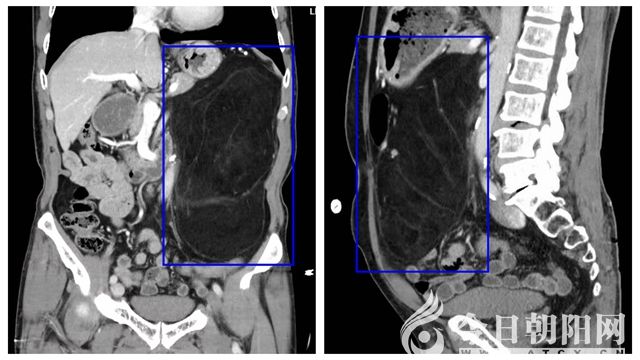

9月17日上午,市二院消化內(nèi)科門診接待了一位特殊的老先生。老先生在體檢行肝膽胰脾彩超檢査后,被告知胰腺區(qū)域大范圍顯示不清、回聲信號異常,建議進一步就診。待行全腹CT檢查后提示:左腎外后方見條形高密度灶,腎周圍血腫或腎包膜下血腫,左側(cè)腹系膜區(qū)見巨大脂肪結(jié)構(gòu)堆積灶,腫瘤將左腎及腹膜后大血管包繞填壓,考慮巨大脂肪瘤。在沒有任何征兆的情況下,平白無故長了一個腫瘤,身體還未受任何影響,這下可急壞了老先生及家屬。在向熟人打聽及上網(wǎng)查詢后,了解到市二院陳亞光主任醫(yī)師領(lǐng)導的胃腸外科團隊在這方面有著豐富的診療經(jīng)驗,便慕名來到該科室。陳亞光主任考慮老先生的疾病為“腹膜后巨大腫物”,需住院手術(shù)切除方可達到最佳的治療效果。就這樣,71歲高齡的老先生在家人的陪伴下,住進了胃腸外科,打響了自己與疾病斗爭的第一槍。

隨著老先生住院后,第一個問題便來到了胃腸外科醫(yī)生面前,CT提示腎周圍血腫或腎包膜下血腫,究竟是怎樣形成的?如果腎周血腫進一步增加,患者可能存在腎出血、腎破裂的可能,隨之而來的就是失血性休克,嚴重危及患者生命安全,手術(shù)中是否能保留患者左側(cè)腎臟等一系列問題擺在了醫(yī)生面前??剖矣懻摵螅⒓唇o予患者完善術(shù)前相關(guān)檢查并組織全院相關(guān)科室會診。檢查及會診后結(jié)果未見血腫進一步增加,血紅蛋自及紅細胞穩(wěn)定,術(shù)中保留左側(cè)腎臟的幾率較高,這樣大家才松了一口氣。待患者完善腹部增強CT后,第二個問題接踵而來,巨大的腫物幾乎占據(jù)了大部分腹腔,大面積小腸腸管受壓,同時腫瘤與周圍組織及周邊大血管關(guān)系密切,手術(shù)切除難度極高。對于此類情況,常規(guī)手術(shù)是要在腹部開一個長約25cm的大切口,將腫瘤切除取出,但是考慮到患者的年齡和特殊血型(B型Rh陰性血,俗稱熊貓血),行開腹手術(shù)創(chuàng)傷大、恢復慢,因此,采用腹腔鏡微創(chuàng)手術(shù)切除更為合適,用最小的創(chuàng)傷,獲得最快最佳的治療效果。

在完善相關(guān)準備后,9月30日18時21分,胃腸外科手術(shù)團隊與麻醉科醫(yī)生通力配合,在全麻下為老先生實施手術(shù)。手術(shù)應(yīng)用腹腔鏡技術(shù),通過四個不足1cm的穿刺孔,全程高清放大顯示下完成整個手術(shù)操作,完整切除腫物兩枚,并通過下腹部小切口將腫物完整取出,兩枚腫物緊密相連,大者約28x19x6cm,小者約14x17x6cm,質(zhì)軟,包膜完整光滑,和術(shù)前診斷一致,為腹膜后巨大脂肪瘤。手術(shù)過程順利,無副損傷,術(shù)中無明顯失血,未進行輸血。